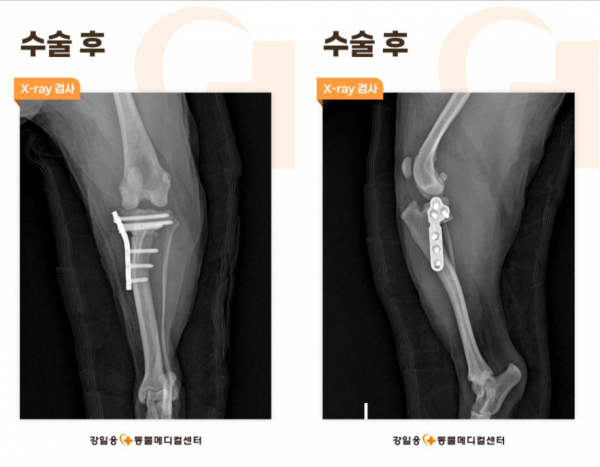

강아지 TPLO

강아지 TPLO 수술은 파열된 인대를 직접 꿰매지 않고

안정성이 생기도록 뼈의 구조를 바꿔주는 수술입니다.

강아지 뒷다리의 정강이뼈(경골)은 위쪽의 관절면이 뒤로 기울어져 있기에,

강아지 십자인대파열이 발생하면 대퇴골이 앞으로 미끄러지며 무릎이 불안정해지게 되는데요.

강아지 TPLO는 이 경골의 기울어진 면을 잘라 회전 시켜 각도를 평평하게 만들어 무릎에

가해져 전방으로 미끄러지는 힘을 없애는 수술입니다.